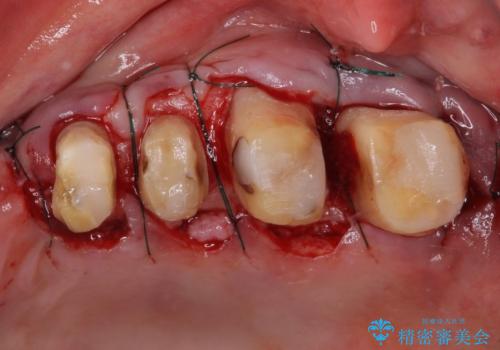

- 歯を磨く度に奥歯から出血するとのことで来院された患者様です。

歯周ポケット検査を行ったところ、6-8mmの歯周ポケットが散見され(正常では3mm以下)、歯周病治療が必要と判断されました。

仮歯に置き替え、歯周外科処置(APF、歯肉弁根尖側移動術)による歯周ポケット除去を行った後に、オールセラミッククラウンにて補綴することとしました。

歯周外科処置により歯周ポケットを除去することができ、クラウン装着後はブラッシング時の出血や歯肉の腫れが気にならなくなりました。